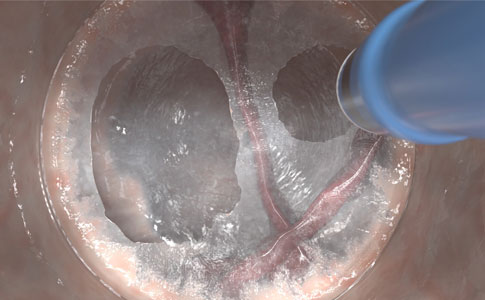

‘PRECISE’ SNIJDEN EN COAGULEREN

Bereik een hoge elektrochirurgische precisie en beperk thermische schade met behulp van de dunne elektrode, pas verschillende coagulatietechnieken toe met VIO® modi.

- Dunne 0,5 mm elektrode voor nauwkeurig snijden met beperkte thermische schade

- Vooral belangrijk voor dunwandige anatomie, bijv. rechter colon

- Diverse distale tip-ontwerpen voor een reeks elektrochirurgische snij-, coagulatie- en weefselmanipulatietechnieken

- Isoleert en legt vasculatuur bloot en drukt bloedvaten samen, waardoor het risico op bloedingen afneemt